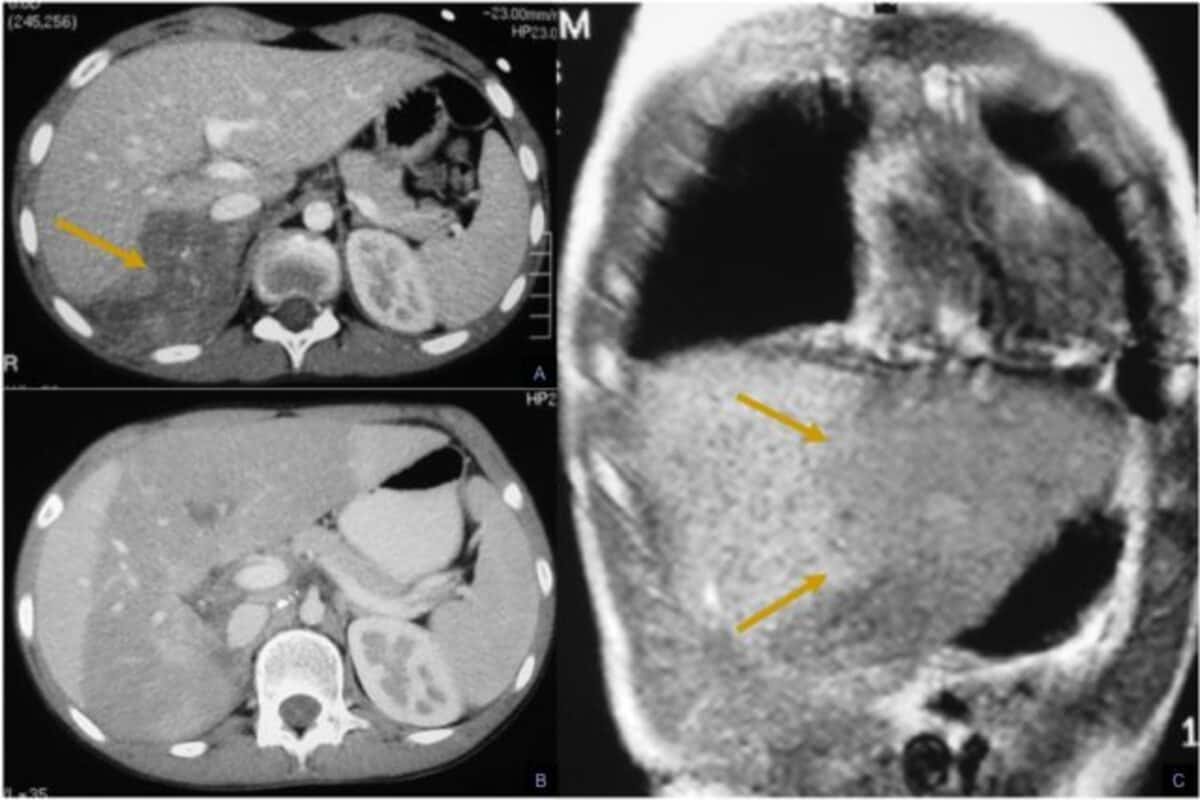

• УЗИ брюшной полости, КТ и МРТ;